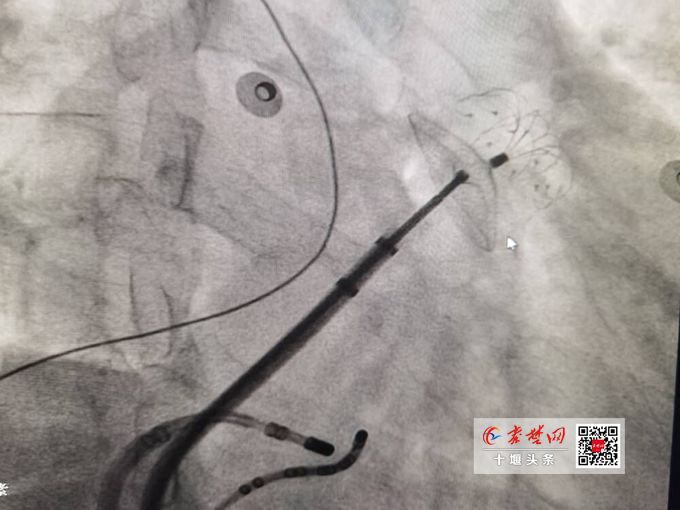

结合潘大爷的既往病史,十堰市人民医院心脏病中心专家团队认为他的房颤已经导致了血栓形成,有非常高的心源性脑卒中复发风险,一旦发病,将有很大概率致死或致残。为有效预防患者房颤复发,并且降低血栓脱落造成脑卒中的风险,同时减少长期服用抗凝药可能带来的出血风险。张友恩博士团队决定为潘大爷进行一站式治疗,即同时为患者实施房颤射频消融术和左心耳封堵术。

“射频消融是一种有效的预防房颤复发的治疗方法,对于维持窦性心律和改善症状是一种安全且优于抗心律失常药物的选择。房颤患者约90%以上的左心房血栓起源于左心耳,所以对于存在抗凝禁忌或出血风险大于获益的患者,左心耳封堵术对于预防由于左心耳血栓导致的相关栓塞疾病是一个有效的治疗措施。”张友恩表示,射频消融联合左心耳封堵的一站式治疗方案,既能为患者提供恢复窦性心律的机会,又能够避免长期服用抗凝药所导致的致命性出血,为患者健康打上“双保险”,是目前房颤治疗领域最为先进的治疗手段。

在与患者及家属充分沟通后,9月下旬,张友恩博士团队先后在局麻下以微创的方式顺利为患者完成房颤射频消融术+左心耳封堵术。手术仅用时2小时余,术后患者感觉良好。这是由十堰市人民医院心脏病中心专家团队成功完成的十堰市首例射频消融联合左心耳封堵治疗房颤的“一站式”手术,标志着十堰市人民医院心脏病中心介入治疗再次取得新突破。